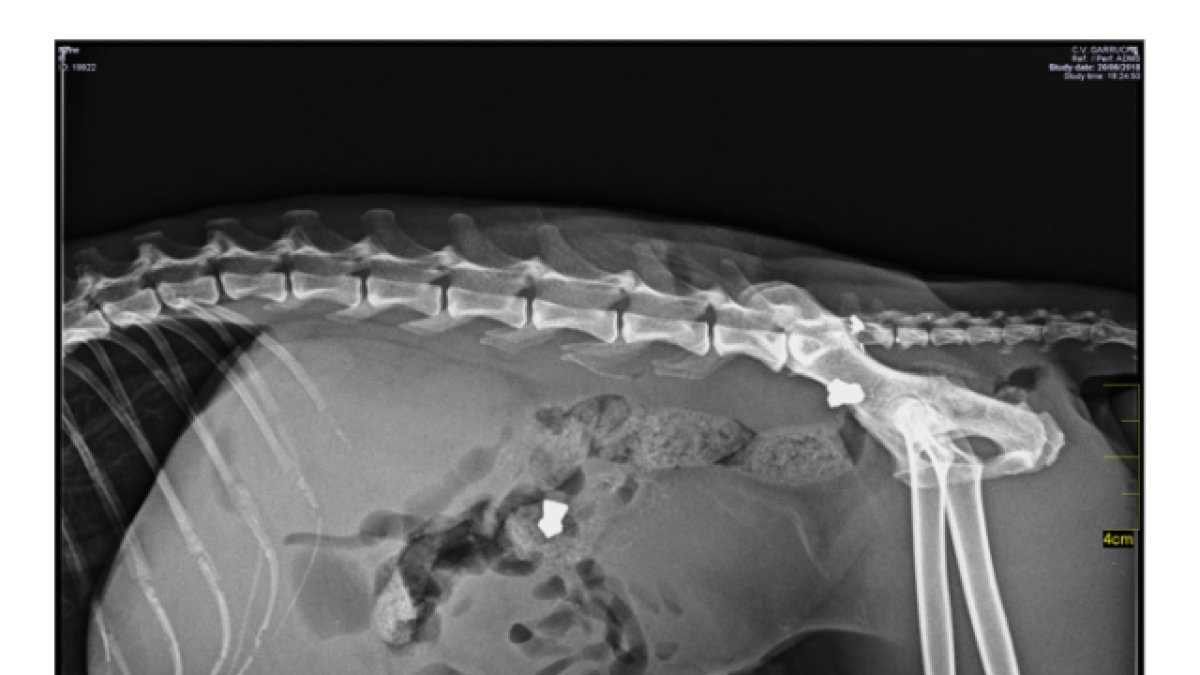

Radiografía donde se pueden apreciar los dos balines en el cuerpo del gato \'Nene\'.

‘Nene’ llegó a casa muy enfermo. “Vino aquí a morir”, cree Alla. En principio, no descubrieron la causa de sus heridas. “Parecía que tenía alguna infección”. Pero una semana después, en una nueva visita al veterinario, le hicieron una radiografía y descubrieron dos balines adosados en su estómago. El informe del veterinario especifica que el gato “ macho blanco y gris presentaba un absceso grande en el costado derecho” y que “durante la exploración se constató que tenía alojados dos balines en el abdomen, causantes de las lesiones que presentaba”. “Por suerte, es un gato muy fuerte, ya que está siempre en la calle, y las balas se quedaron en la musculatura, no llegaron a afectar a ningún órgano”, explica su dueña.

‘Nene’ tuvo que ser operado para extraerle los proyectiles. Una intervención complicada y costosa. “Eran balines con punta afilada, no redondeados”, denuncia Dolgaleva. Por el momento se desconoce quien pudo ser el autor de los disparos ni si hubo algún testigo que pueda ofrecer más información.